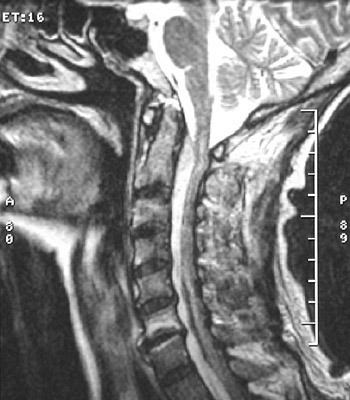

In the sagittal MRI scan view above can be seen a fluid collection not as bright as the normal CSF with the T2 weighted scan on the left, demonstrating an

epidural abscess

. With the T1 weighted scan below can be seen the same epidural abscess.